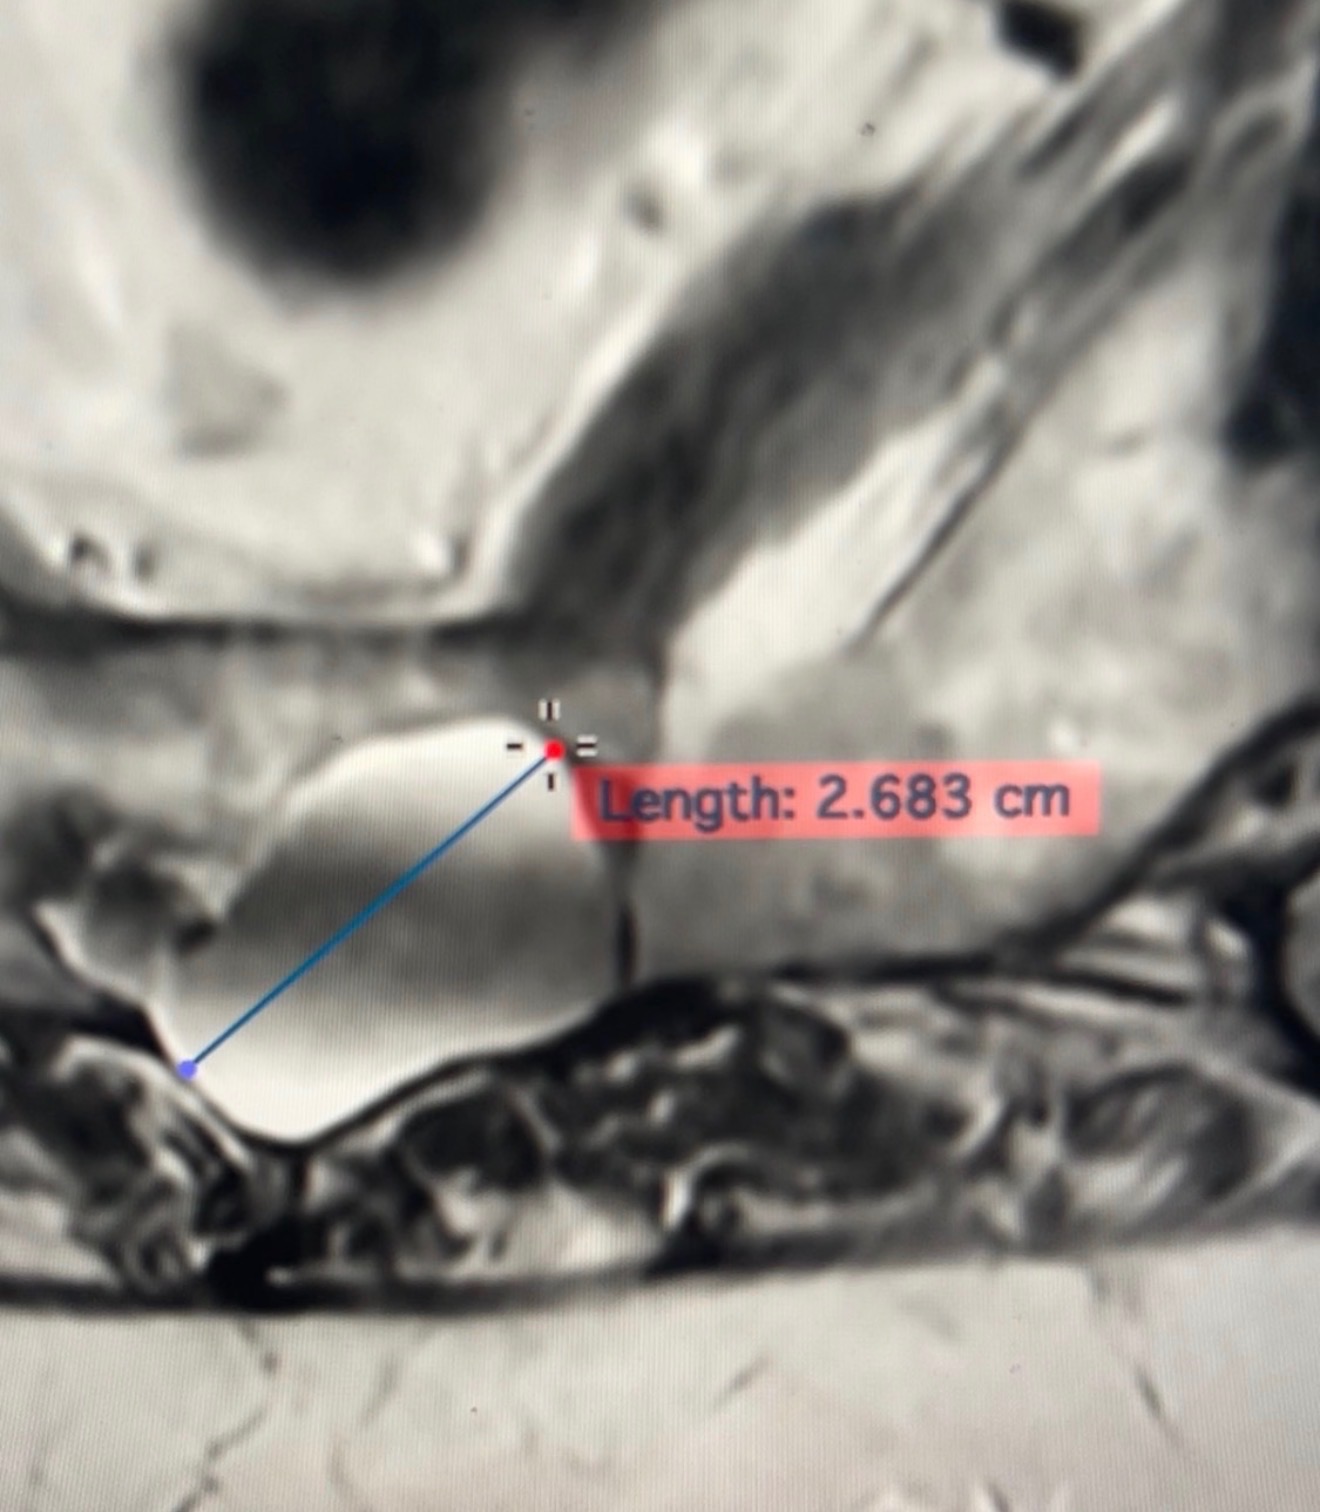

Over the past year, Karen has been living with severe, crippling pain caused by a tarlov cyst on her spinal cord, along with advanced lumbar degenerative disc disease, severe facet osteo arthritis in the lumbar spine and neuro stenosis on her L3, L4 and L5 joints. She has seen multiple doctors and specialists and has undergone X-rays, MRIs, and several CT scans. In an effort to manage the pain, she has undergone multiple cortisone injections— none of which have brought lasting relief. After multiple consultations she was also not a candidate for nerve ablations.

Recently, doctors discovered that the cyst on her spine is progressing and is now dangerously close to leaving her wheelchair-bound. She is unable to stand for more than 10 minutes at a time and lives in constant pain, day and night. She cannot lie flat, struggles to sleep, and her quality of life has been deeply affected.